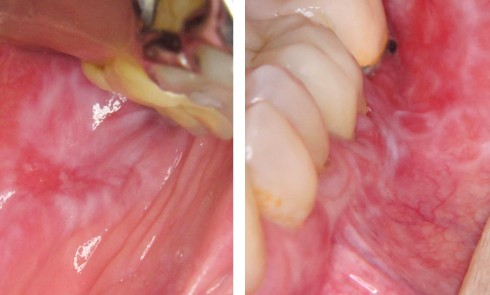

Article réservé à nos abonnés Lésion blanche : pourquoi rester vigilant ?

Situation clinique Anamnèse. Une patiente âgée de 73 ans est reçue en consultation pour un avis en raison de la...